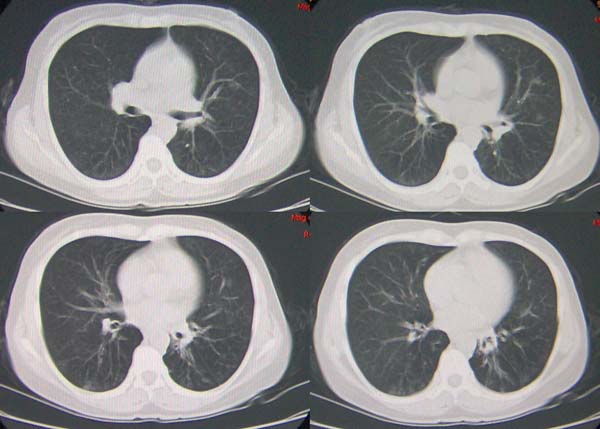

左肺下叶支气管呈囊状扩张。考虑支扩。

左下肺支气管扩张;支气管炎;左下肺纤维条索并局部胸膜肥厚。

左肺下叶支气管呈囊状扩张。考虑支扩。胸膜肥厚\\粘连,建议增强除外肺隔离症.

左肺上叶小片状病灶密度底,左下叶见多发小囊状病灶,周围透光增强无纹理,沿左侧膈肌旁见条带状病灶边界清晰,

1左肺上叶炎症,左下支气管扩张伴感染,肺隔离征待除外,2肺大泡,3左下叶内基底段不张?

左肺上叶舌段炎症,左肺下叶支气管扩张并感染

左肺舌叶及右肺下叶背段斑片状低密度影,左肺下叶内基底段网格状阴影,周围肺野透亮度增高,结合临床咳嗽、发热,38度,无咯血及反复感染病史,考虑双肺炎症,左下肺发育不良。建议抗炎治疗后复查或增强与左下肺隔离症鉴别。